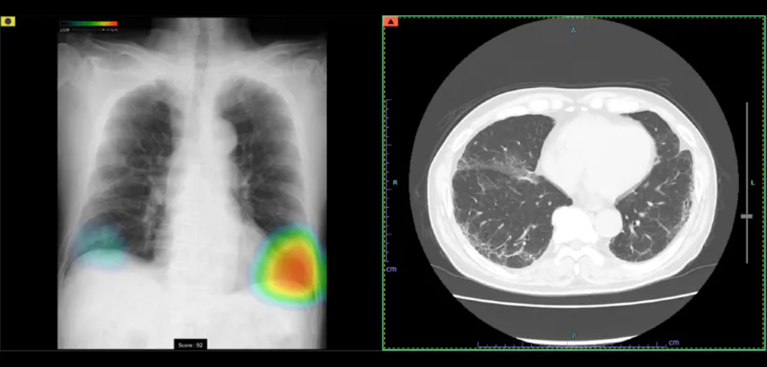

AI診断システムCXR-AID(富士フィルム社)を導入しております。胸部レントゲン画像をAIによって解析し、結節や腫瘤陰影・浸潤影(炎症)・気胸などが疑われる場合、色付けによって表示されます。これにより医師とAIのダブルチェックが可能となり見落としのリスク軽減・初期段階でキャッチできるなどのメリットがあります。

CXR-AIDは、AIが胸部の画像を数十秒で読み取り、気になる可能性のある部分をマークして表示します。医師はAIが示した箇所を確認しながら診断を行うため、見落としが少なく、より正確な診断につながります。AIと医師が一緒にチェックすることで、病気を早めに見つけられる体制を整えています。

検出対象となるのは、主要な肺疾患に関連する画像所見である「結節・腫瘤影」、「浸潤影」、および「気胸」の3つです。

0~100に分けられた確信度スコアの最大値が数値として表示されます。

胸部レントゲン所見のスコア値が中間である場合、治療が必要かどうかの判断が難しい状態です。中間の数値が出た場合には、1~数ヶ月後に再度の胸部レントゲン撮影を行い、スコア値に変化がないかを確かめます。スコア値が増えている場合には治療を必要とする病変の可能性が高くなります。